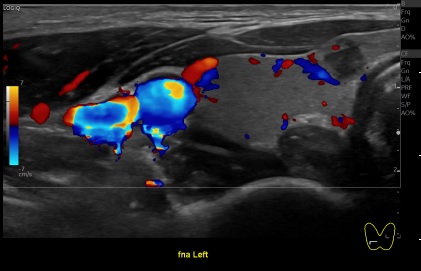

상기환자 외부검사이상 세침검사위해 내원하신 30대초반 여성분으로

의심스러운 갑상선 좌엽 결절 세포검사 진행후 갑상선암으로 진단되었습니다